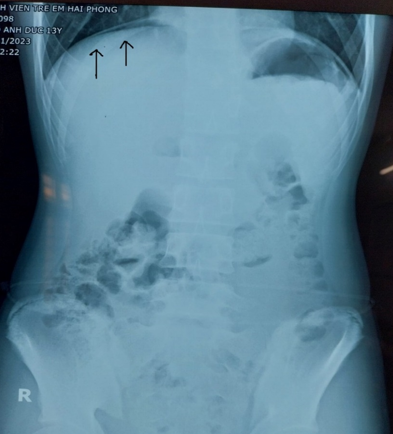

Xquang của bệnh nhân có liềm hơi dưới cơ hoành, dấu hiệu của thủng tạng rỗng